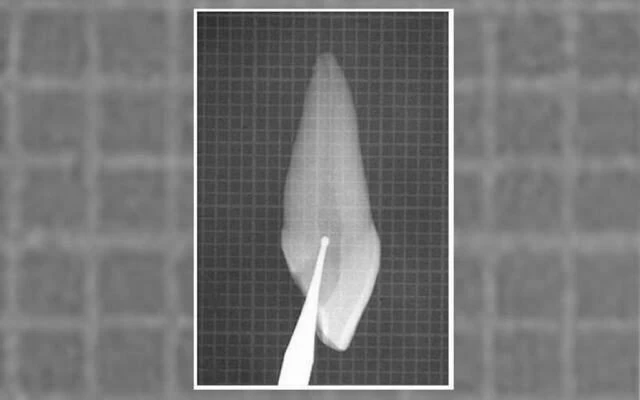

Trên X-quang có thể thấy chân răng hơi cong nhẹ theo chiều gần xa hoặc ngoài trong (hình 5.41).

Phim X-quang điều trị của răng cửa giữa hàm trên bên phải

Hình 5.41. A. Phim X-quang trước điều trị của răng cửa giữa hàm trên bên phải. Lỗ chóp nằm trên cùng một mặt phẳng trên đường đi của tia X: nó có thể đối diện với mặt trong hoặc mặt ngoài. B. Phim X-quang thứ hai chụp theo hướng gần-xa cho thấy đoạn cong đối diện với mặt ngoài. Việc điều trị tủy được hoàn tất, giữ nguyên góc chụp cho phép nhìn thấy được điểm cuối cùng trên X-quang của ống tủy. C. Phim sau điều trị. Lưu ý rằng chỉ với góc chụp này mới thấy được hình ảnh tổn thương nhỏ tại chóp chân răng. D. Phim sau điều trị được chụp theo tiêu chuẩn hình chiếu. Lưu ý rằng vật liệu trám ống tủy dường như bị ngắn đi chừng 2mm và tổn thương cũng đã lành.